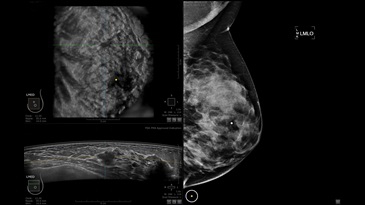

GE INVENIA ABUS – это современный УЗИ аппарат, который создан для точной и эффективной диагностики сканирования с высокой плотностью молочных желез. Выявляемость патологий раковых и предраковых стадий заболевания составляет 55%, что в конечном счете позволяет ставить врачу точные и своевременные диагнозы. Традиционные методы использования маммографии не показывают такой выявляемости, ограничиваясь лишь 3-38%.

• Получение изображений в поперечной плоскости (в реальном времени) и в коронарной плоскости (статическая, для указания нахождения соска)

• Отображение объемных 3D ультразвуковых изображений, которые состоят из традиционных поперечных и воссозданных коронарных и сагиттальных проекций

• Стандартизованная ориентация изображения: «толстый срез» в коронарной плоскости; поперечная; сагиттальная плоскость; радиальный и антирадиальный поворот изображения; просмотр исключительно области интереса